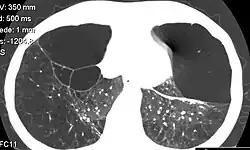

| CT scan of the lung showing bullae in the lower lung lobes of a subject with type alpha-1-antitrypsin deficiency. There is also increased lung density in areas with compression of lung tissue by the bullae. | |

A focal lung pneumatosis is an enclosed pocket of air or gas in the lung and includes blebs, bullae, pulmonary cysts, and lung cavities. Blebs and bullae can be classified by their wall thickness.[1]

- A lung cyst has a wall thickness of up to 4 mm.[2] A minimum wall thickness of 1 mm has been suggested,[2] but thin-walled pockets may be included in the definition as well.[5]

Lung cysts are seen in about 8% of the general population, with an increased prevalence in older people, and are not associated with emphysema.[5] They may be part of the aging changes of the lungs, and cause a slight decrease in their diffusing capacity.[5] The presence of multiple pulmonary cysts may indicate a need to evaluate the possibility of bullous or cystic lung diseases.[5] Cavitation indicates workup for serious infection or lung cancer.